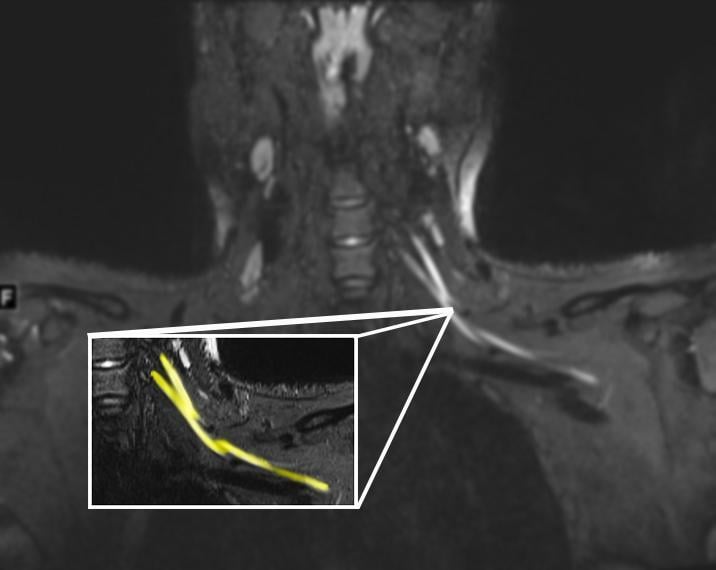

This photo gallery shows the variety of radiological presentations of COVID-19 (SARS-CoV-2) in medical imaging, including computed tomography (CT), radiograph X-rays, ultrasound, echocardiograms and magnetic resonance imaging (MRI). The radiology images show examples of typical COVID pneumonia in the lungs and the numerous complications the virus causes in the body in multiple organs, including the brain, kidneys, heart, abdomen and vascular system.

Ultrasound, especially hand-held ultrasound imaging devices, have become a primary imaging modality for novel coronavirus because of the ease to bag the device and sterilize it after use. CT and mobile X-ray systems are also used as front-line imaging systems for COVID-positive or suspected COVID patients.